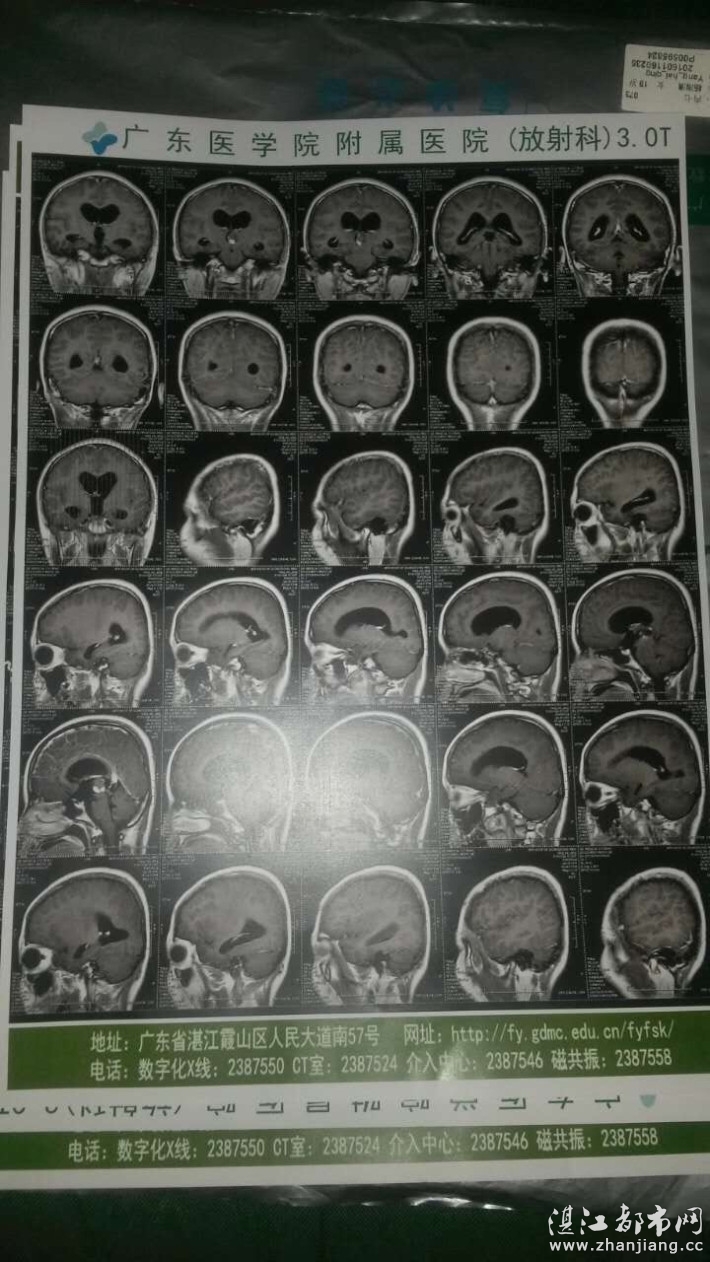

大家(帮助这位花季少女吧!才十八岁的女学生,人生才刚刚开始,却被病魔缠身,恳求各位好心人,帮帮这同学脱离苦海吧!今年才18岁。本以为18岁的青春,应该会和其他同学一样充满阳光,努力学习,为自己的人生憧憬未来。但命运似乎跟这个平凡的女孩开了一个玩笑。。。)该患者叫杨海清,是广东省雷州市南兴镇清尼村人。目前在广东三九脑科医院接受治疗,现在医生诊断为是脑肿瘤,必 须马上手术,一开始,由于病情严重,1月15日从湛江市广东医学院附属医院转到广州市三九脑肿瘤内科治疗,最终确诊为脑肿瘤,和脑内积水,肿瘤体积很大,而且癌细胞有扩散迹象,由于本身体质比一般人差,继而引发一系列并发症,现在身体每况越下,医生说必须马上化疗缩小肿瘤才能做切除手术,才能续命。目前已经动了三次大手术,手术过程中脑内几处多次出血,情况危急,目前还处于昏迷之中,还未度过危险期。但是住院治疗这段时期已经花光家庭所有积蓄,爸爸只是一名送煤气工人,工资低微,两个弟弟还在读初中,家里可以卖的都卖了来垫付医药费,之前亲戚朋友凑合的资助款也用完了,能借的都借过了。面对几十万如此庞大的医疗费用,这一个普通的农民家庭实在是无计可施。每天看着该母父为愁钱痛苦的样子,旁人看了也百般不好受。现在求求各位好心人,各位哥哥姐姐,叔叔阿姨,求求你们帮帮她们,救救她的家庭吗?哪怕是一元钱,只要有您的帮助,她们就多一份生存的希望了。她和家人必将万分感激,相信这个朴实的农民家庭日后定会回报社会,答谢今天好心人为她们献出的爱心。得人恩惠千年报,你们的善举,一辈子都会铭记于心。感谢有您!